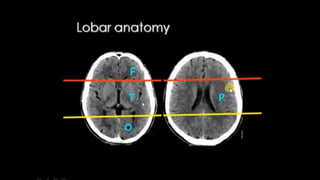

LOBES

TEMPORAL LOBE CONTOURING Francis Ho, MEDICEINE,2018